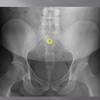

posterior arch of C1

How well did you know this?

1

Not at all

2

3

4

5

Perfectly

10

Q

A

lamina c2-c7